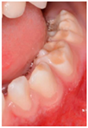

IMAGE 3![]() | Dental caries | 294 (81.9) |

| Enamel defects | 53 (14.8) | |

| No dental lesions | 12 (3.3) | |

| I do not know | 0 (0.0) | |

| IMAGE 3 | ||||||

| Caries | 102 (28.4) | 83 (23.1) | 66 (18.4) | 37 (10.3) | 6 (1.7) | p < 0.05 |